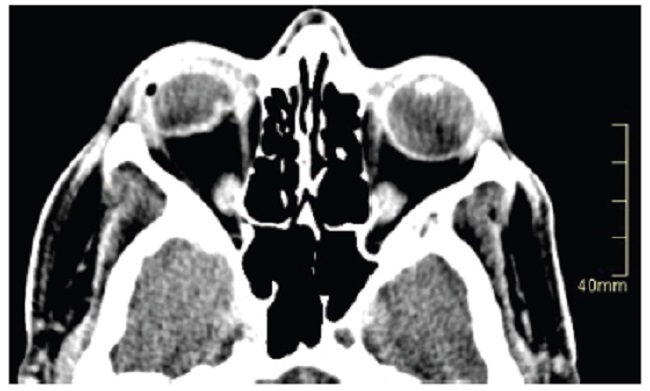

Las calcificaciones oculares y el material médico se pueden confundir con cuerpos extraños u otras lesiones orbitarias1. Las localizaciones típicas de las calcificaciones permiten diferenciarlas de cuerpos extraños hiperdensos. Las más frecuentes son las calcificaciones trocleares, las placas esclerales, las drusas del nervio óptico y la ptisis bulbi. Las primeras tienen localización superomedial dentro de la órbita (Fig. 13), en la tróclea del músculo oblicuo superior, aunque se pueden observar en todas las edades, hay mayor prevalencia de calcificaciones trocleares en pacientes con enfermedades autoinmunes y niveles elevados de fosfatasas alcalinas. Las placas esclerales se localizan en los sitios de inserción de los músculos rectos medial y lateral (Fig. 14) y son más comunes en los pacientes ancianos. Las calcificaciones que ocurren cerca del disco óptico se conocen como drusas del nervio óptico (Fig. 15), las cuales se asocian a degeneración macular y pueden ser causa de pseudopapiledema benigno. La ptisis bulbi es una atrofia y calcificación del globo ocular como secuela de enfermedades infecciosas, inflamatorias o traumáticas previas (Fig. 16) (1,11. Los imitadores de lesiones abiertas del globo ocular incluyen las deformidades como coloboma, estafiloma y el globo ocular elongado por glaucoma o miopía (Fig. 17). Las masas orbitarias y los hematomas también pueden alterar el contorno del globo ocular y asociarse a calcificaciones o relacionarse con desprendimiento de retina (Fig. 18) (1,6,8,11.

Los cambios postratamiento y los dispositivos orbitarios también pueden malinterpretarse como patologías traumáticas. Dentro de estos cambios se incluyen la faquectomía con reemplazo del cristalino, las hebillas esclerales (Figs. 19 y 20), las inyecciones intraoculares de aceite de silicona, la retinopexia neumática y las prótesis de globo ocular1,6,11. Para diferenciar la silicona intraocular de hemorragia se ha propuesto la medición de las UH, siendo la atenuación > 100 UH sugerente de silicona y < 90 UH de sangre11 (Fig. 20).